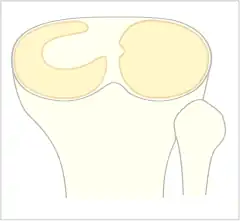

• Top:Discoid lateral meniscus

The Watanabe classification of discoid lateral meniscus is: (A) Incomplete, (B) Complete, and C) Wrisberg-ligament variant [2] Normally, the meniscus is a thin crescent-shaped piece of cartilage that lies between the weight bearing joint surfaces of the femur and the tibia. It is attached to the lining of the knee joint along its periphery and serves to absorb about a third of the impact load that the joint cartilage surface sees and also provides some degree of stabilization for the knee. There are two menisci in the knee joint, with one on the outside (away from midline) being the lateral meniscus and the inner one (towards midline) the medial meniscus. A discoid meniscus is a congenital anomaly of the knee found in 3% of the population (up to 15% in Asia). It typically affects the lateral meniscus and may be found bilaterally (20%). Instead of the narrow crescent shape, as seen in a normal meniscus above, a discoid meniscus is thickened, and has a fuller crescent shape. In addition, a discoid meniscus does not taper as much towards the center of the joint and is shaped like a disc. The thickness of the meniscus, its diminished vascular blood supply, and in some instances, weak capsular attachment, makes it more prone to tears compared to a normal meniscus. The anomaly in itself is asymptomatic; however, a tear of the meniscus can result in pain, swelling, and snapping in the affected knee. The orthopedic classification of discoid menisci includes: complete, incomplete or Wrisberg-ligament types as depicted here. Coverage of the lateral tibial plateau determines the designation of complete or incomplete. The Wrisberg-ligament type has an abnormal posterior attachment by attaching to part of the posterior cruciate ligament.